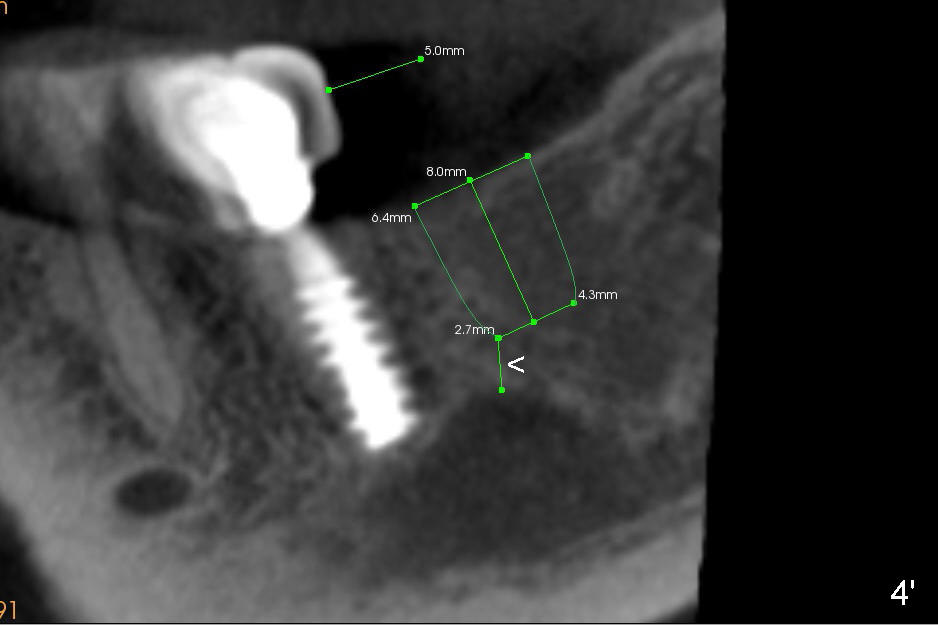

To avoid nerve injury, the implant should be 2 mm shorter or placed at the level of the original crest top (Fig.4,4').  There is 4 mm from the main nerve trunk (Fig.4) or 2.7 mm from the bulging segment of the nerve sagittally (Fig.4' <).   The exposed buccal (B) and lingual top microthreads will be covered by autogenous bone graft, harvested during reamer osteotomy.  If not enough, allograft is supplemented.  The bone graft is then covered by collagen membrane, which is fixed between the implant and a healing abutment.